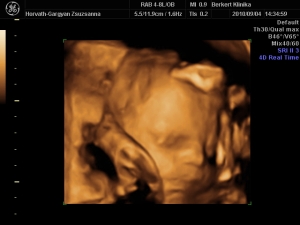

nagyon jó eltelt a szombatunk a drága férjemmel, későn keltünk, egy kis fincsi sült császár szalonnás reggeli tükör tojással...aztán takarítás, csodaszép idő volt ma...2-re mentünk a 4D-s uh-ra :!: :wink:

Valami fantasztikus volt :lol: annyira jól éreztük magunkat, Cipike annyira kis izgága babó, hogy alig lehetett követni mikor merre van, de sikerültek a képek és a DVD-s...egyszerűen nem tudunk vele betelni, már 2-szer megnéztük és még mindig ámulunk és bámulunk :!: :roll: :wink: Sztem az arca totál rám hasonlít, apácska el is volt keseredve :roll: :wink:

Minden a legnagyobb rendben van Cipikével, már 1140 g és csodaszép kis kukis :!: :wink:

És egy pár kép a 4D-ről...

Kép ARC

Kép KUKI, oda is van írva, csak a kicsinyítés miatt nem nagyon lehet elolvasni :!: :roll: :wink:

Kép MOSOLY